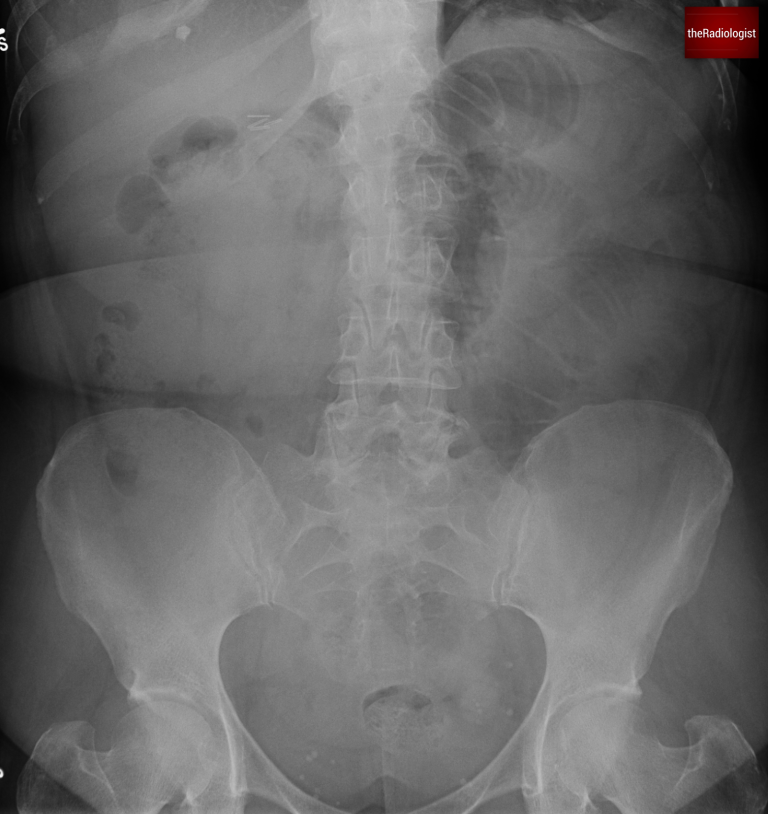

A female in her 60s presents with abdominal pain. There is a history of previous abdominal surgery, diabetes mellitus type II and atrial fibrillation. Have a look at the abdominal X-Ray below.

Abdominal X-Ray on presentation

We can see some prominent bowel loops in the centre of this film suggesting there may be bowel obstruction. How can we tell the difference between small and large bowel obstruction?